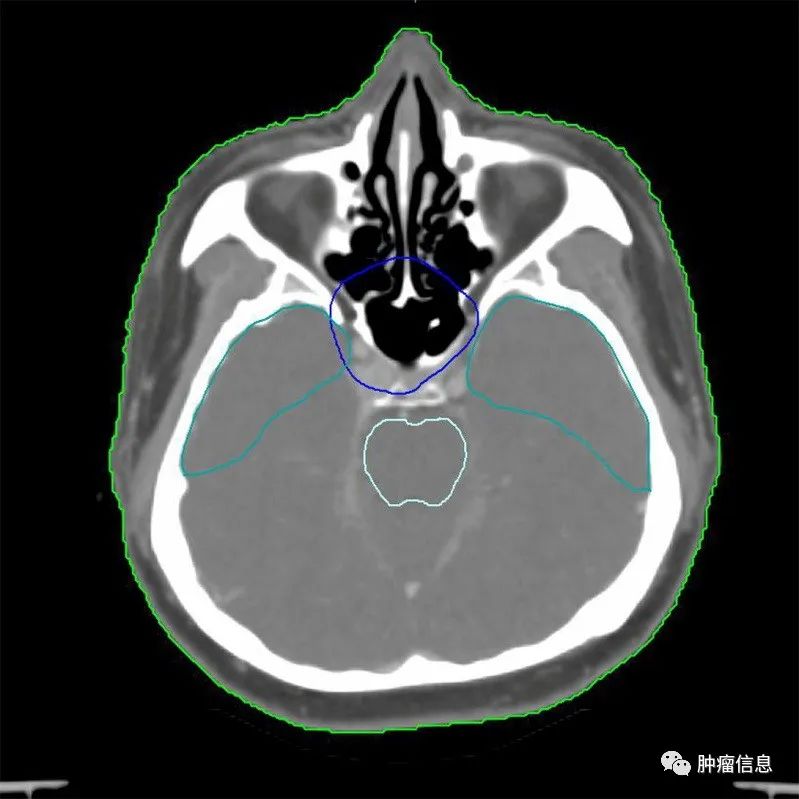

2.靶区勾画示意图

为方便和国际指南对照,靶区采用与国际指南相同的颜色:国际指南的GTVp =本示意图GTVnx;国际指南的GTVn =本示意图GTVnd;国际指南的CTV1 =本示意图CTV1;国际指南的CTV2 =本示意图CTV2。

图1 T1N0M0

(注:靶区勾画颜色, GTVnx为红色,CTV1为绿色,CTV2为蓝色。)